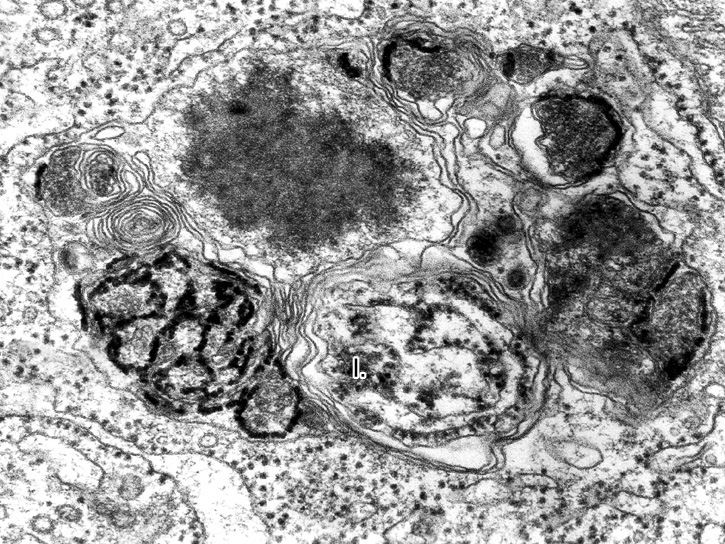

Sokan gondolják, hogy az autofágia pusztán azt jelenti, hogy ha a sejt elkezd éhezni, mindenáron táplálékhoz akar jutni, ezért lebontja önmagát. Ez azonban túlzott egyszerűsítés,

az autofágia lényege sokkal inkább a felépülés és a lebomlás dinamikus egyensúlya.

Az erről szóló elmélet az 1960-as években látott napvilágot, a jelenséget azonban nehéz volt tanulmányozni. Így egészen az 1990-es évek elejéig keveset tudtak róla, amikor is Oszumi Josinori áttörést ért el úttörő kísérleteivel, amelyekkel azonosította az autofágiában alapvető fontosságú géneket.

Eredményei paradigmaváltáshoz vezettek a sejten belüli újrahasznosítás, valamint az autofágia sok fiziológiai folyamatban – játszott szerepének megértésében – főként az éhezéshez való alkalmazkodásban, illetve a fertőzésekre adott reagálásban. Az autofágia finomműködésének megértését egyébként rengetegen vizsgálják olyan területeken is, mint az öregedéskutatás, az Alzheimer-kór vagy a rák.